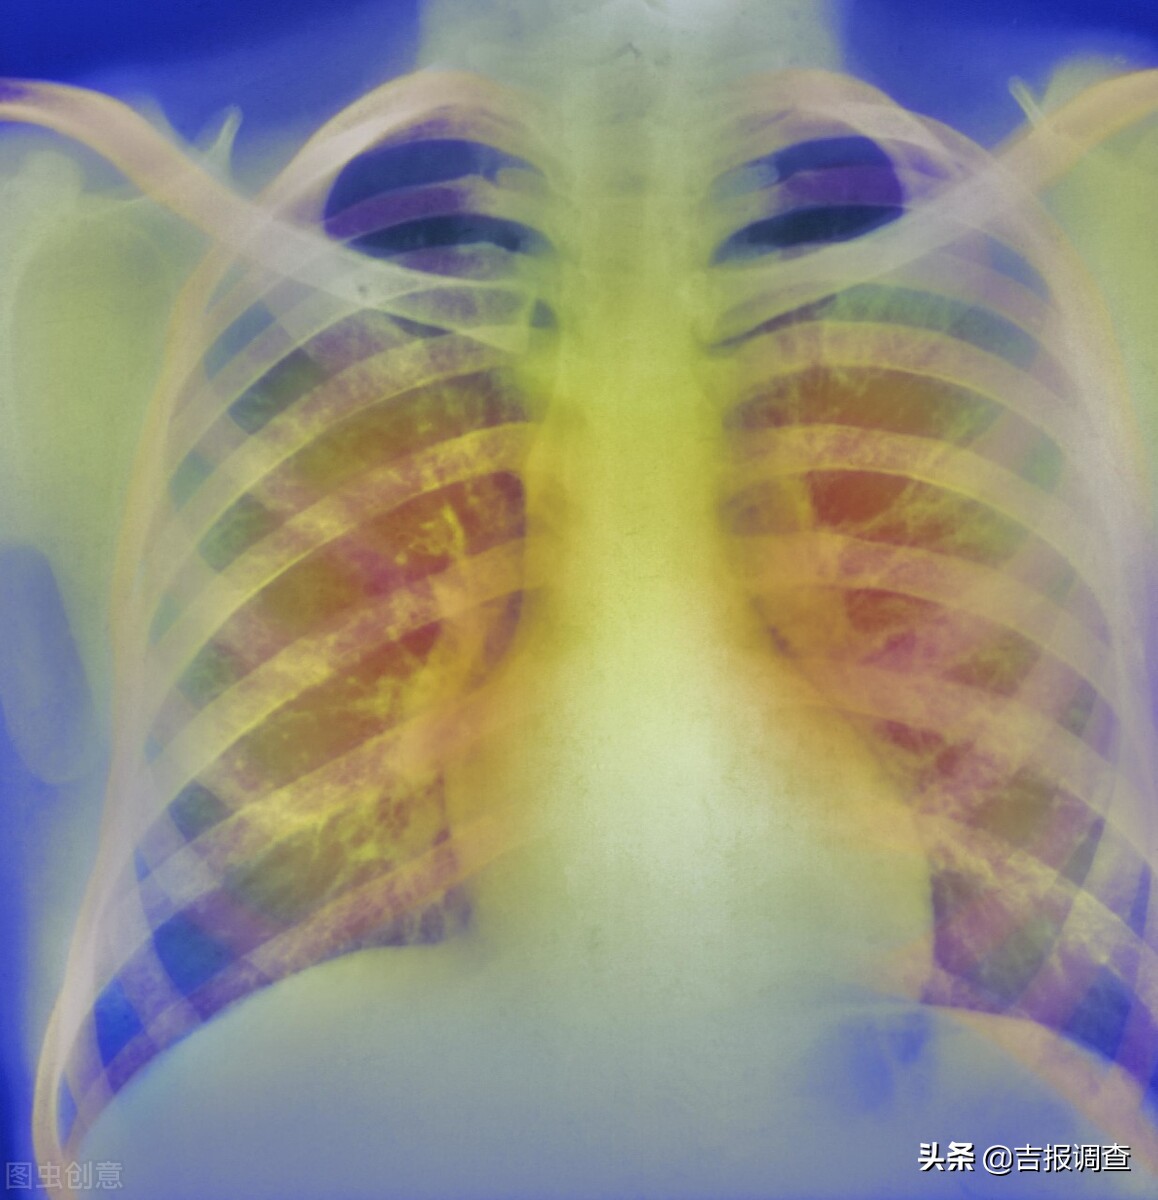

慢性肺病大多病程较长,病情复杂。慢性支气管炎、慢阻肺、支气管哮喘、肺源性心脏病等疾病,多是由肺系急性病变未及时适当治疗,或原本体质虚弱,反复感染外邪迁延发展而致。夏季气温升高,人体血液循环较好,慢支炎、肺气肿、支气管哮喘等病症表现往往不明显,致使许多患者产生疾病好转的错觉,从而放松警惕,如不及时治疗,常常会失去治疗的最好机会,此时如果忽视对疾病的巩固治疗,对于各类慢性肺病患者来说,是极其不利的。